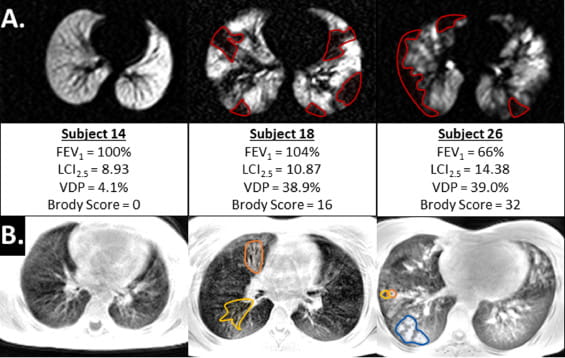

Hyperpolarized Xe gas is emerging as an inhaled contrast agent of assessing pediatric lung disease, and our group is working to improve all aspects of Xe MRI including engineering solutions for faster Xe gas production with higher MRI signal, designing MRI pulse sequences for faster acquisition with shorter breath-holds, and adapting Xe MRI techniques for younger children.

Our team was the first to demonstrate Xe MRI was safe in children and feasible even in children who are unable to perform spirometry, the clinical gold-standard test for lung disease. We recently demonstrated that Xe gas-transfer MRI, a technique that provides regional measurement of pulmonary gas exchange in adults, was feasible in pediatric populations and detected membrane-uptake and red-blood cell transfer abnormalities in children with lung disease.